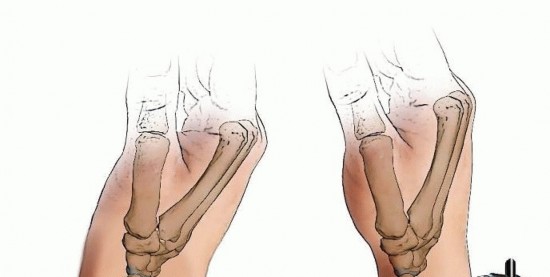

Distal radius fractures occur at the distal end of the bone, originating in the metaphyseal region and often extending to the radiocarpal and distal radioulnar joints (DRUJ).Distal radius fractures can be classified as stable or unstable and extra- or intra-articular to assist in treatment decisions.Fractures may angulate dorsally or volarly and may have significant comminution depending on the energy of the injury and the quality of the bone.Percutaneous pins or K-wires, typically 0.062 or 0.045 inches, can be used for treatment of simple intra-articular or extra-articular fractures with mild comminution and no osteoporosis.Percutaneous pins can aid reduction and stabilize the fragments in a minimally invasive manner.Percutaneous pins can support the subchondral area of the distal radius and maintain the articular reduction in highly comminuted fractures, which is useful when combined with other fixation methods.Smooth percutaneous pins may also be placed across the physis to maintain a reduction in children with minimal risk of a growth arrest.Highly comminuted fractures are more difficult to fix rigidly and often require external and/or internal fixation to maintain alignment during healing.External fixators can be hinged or static and may or may not bridge the wrist joint.K-wire fixation of extra-articular and simple intra-articular fractures has received more support over the last few years after several prospective randomized trials comparing K-wire fixation to volar plating has shown no difference in outcome at 1 year. FIG 1 • Anatomy surrounding the radial sensory nerve branch in the forearm.

The distal radius consists of three articular surfaces: the scaphoid fossa, the lunate fossa, and the sigmoid notch.Ligamentotaxis aids in the reduction of intra-articular and comminuted fractures.Volar extrinsic ligamentous attachments include the radioscaphocapitate, long radiolunate, and short radiolunate ligaments.Dorsal extrinsic ligamentous attachments include the radiotriquetral ligament.Dorsal and radial to the second metacarpal lie the first dorsal interosseous muscle and the terminal branches of the radial sensory nerve.The distal radial sensory nerve branches lie superficial to the distal radius and should be protected during dissection and pin placement.The radial sensory nerve emerges between the brachioradialis and the extensor carpi radialis longus (ECRL) muscle bellies ( FIG 1).The terminal branches of the lateral antebrachial cutaneous nerve lie superficial to the forearm fascia at the radial wrist.There is a bare spot of bone between the first and second dorsal compartments in the region of the radial styloid.The brachioradialis tendon inserts onto the radial styloid deep to the first dorsal compartment.The ECRL and the extensor carpi radialis brevis (ECRB) lie dorsal to the brachioradialis in the second dorsal compartment.Lister tubercle is dorsal, with the extensor pollicis longus (EPL) tendon on its ulnar side, in the third dorsal compartment.P.253The extensor digitorum communis tendons lie over the dorsal ulnar half of the distal radius in the fourth dorsal compartment.The extensor digiti minimi lies over the DRUJ in the fifth dorsal compartment.